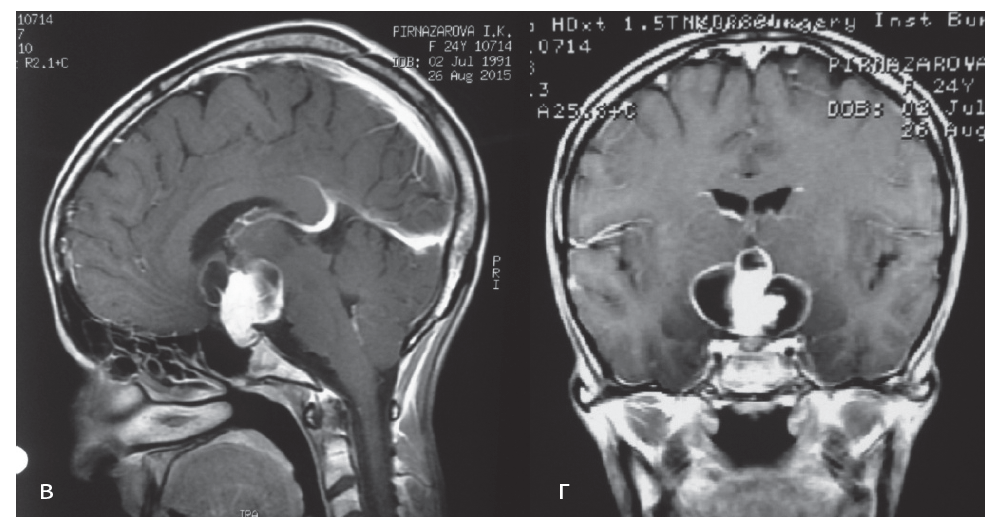

5. Fig. 3. MRI of patient P. 24 years old with contrast enhancement in T1 mode in sagittal (in) and frontal (d) projections before surgery. | |